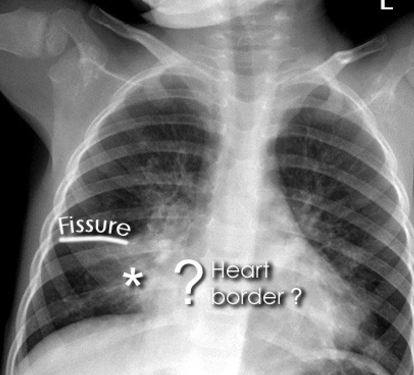

lingular pneumonia

L heart border obscured L hemidiaphragm intact

what does this show

RML collapse